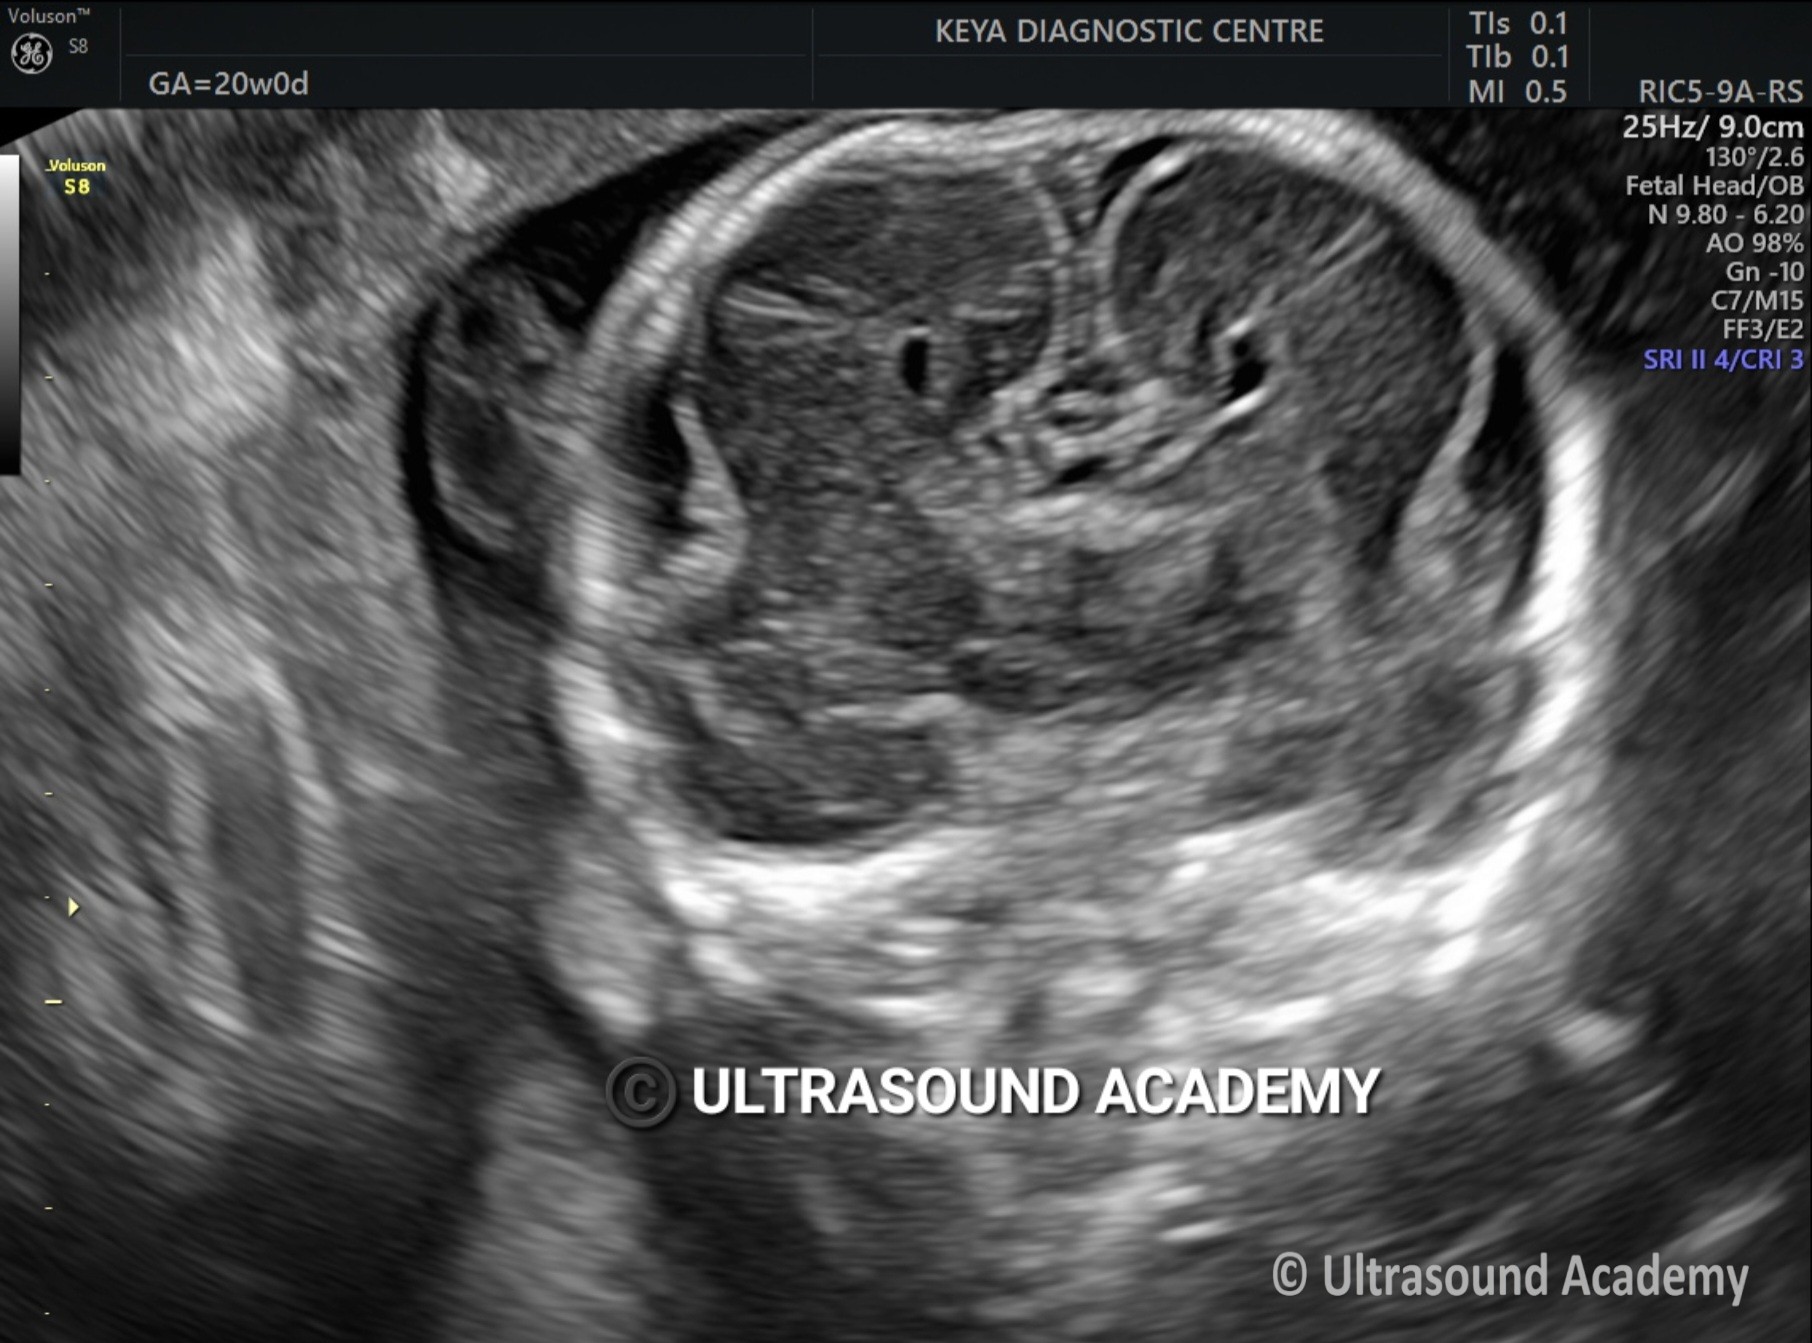

CORPUS CALLOSUM AGENESIS

Findings : Absence of corpus callosum. Frontal horns appears widely separated, Absence of CSP.

Ultrasound findings on ultrasound :

·         third ventricle 5

o    dilated

o    can be elevated or dorsally displaced 8

o    may communicate with the interhemispheric cistern

o    may project superiorly as a dorsal cyst

o    choroid may be seen as an echogenic structure in the roof of the cyst